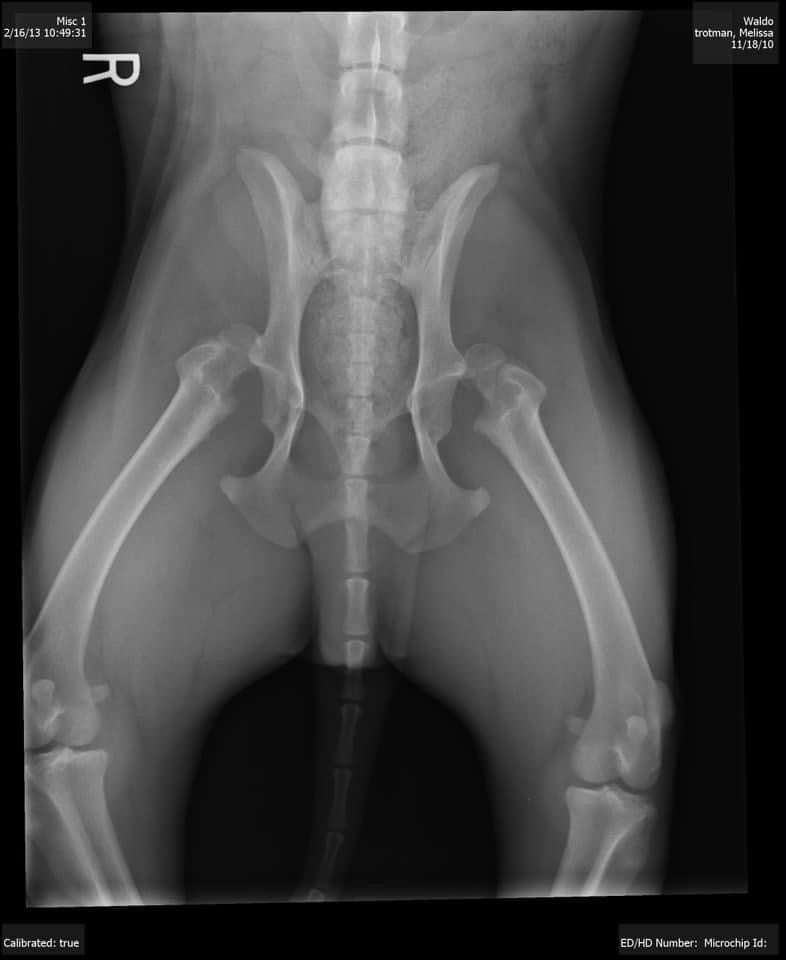

x-ray of a dog with a hip dislocation from dysplasia

Caring for Your Canine: Conservative Treatment for Hip Dislocation in Dogs

Something that might seem daunting but has a ray of hope—hip dislocation in dogs and how you can help them recover with a gentle, conservative treatment approach using the DogLeggs Ehmer Sling. Understanding Hip Dislocation in Dogs First, let's understand what we're dealing with. A hip dislocation, or coxofemoral luxation, occurs when the head of the femur (the thigh bone) slips out of the socket in the pelvis. This can happen due to trauma, such as a fall or a car accident, and is quite painful for our canine companions. Signs to watch for include limping, difficulty standing or walking, and obvious discomfort. When a favorite Golden Retriever patient, Max, had a hip dislocation, his owner was beside herself with worry. Surgery seemed like the only option, but then a vet introduced her to a non-invasive treatment—the DogLeggs Ehmer Sling. What is the DogLeggs Ehmer Sling? The DogLeggs Ehmer Sling is a specialized device designed to immobilize a dog's leg, ensuring the hip joint stays in place and allowing it to heal naturally. It's a soft, comfortable sling that wraps around the dog's body and leg, holding the leg in an elevated position. This helps prevent further displacement and aids in the natural healing process. Why Choose Conservative Treatment? Choosing conservative treatment over surgery can be a great option for many reasons: Non-Invasive: No surgery means no surgical risks and no long recovery from an operation. Cost-Effective: It can be less expensive than surgical options. Comfort: The sling is designed to be comfortable and allows for some mobility, reducing stress for your dog. Bonding Time: Caring for your pet during this period can strengthen your bond, as you play an active role in their recovery. Their Journey with the Ehmer Sling When Max was fitted with the DogLeggs Ehmer Sling, the owner was initially nervous. How would he adapt? Would he be in pain? But the vet assured her that with proper use and care, Max could heal effectively without the need for surgery. Here are a few tips from thier experience: Create a Comfortable Space: Set up a cozy, quiet area where your dog can rest comfortably. Keep their favorite toys and blankets nearby. Follow the Vet's Instructions: Ensure the sling is fitted correctly and keep it clean. Monitoring the fit through the day will maximize its effectiveness. Regular check-ups with your Vet are essential to monitor progress. Supervise Activities: Max needed to be supervised closely to prevent sudden movements. Short, gentle walks were fine, but jumping or rough play was off-limits. Many pets need to be on a leash for the best level of control. Keep Them Engaged: Use puzzle toys or gentle games to keep your dog mentally stimulated. Max loved his treat-dispensing toys during this time. The Road to Recovery Over several weeks, Max adjusted to the sling. The initial discomfort gave way to acceptance, and I could see improvements. His limp lessened, and his spirits lifted. Regular vet visits confirmed that his hip was healing well. The day the vet told the owner that Max's hip had healed sufficiently and the sling could come off was a joyous one. Max was back to his playful self, and they were relieved and grateful for the conservative treatment option. A Few Final Thoughts If your dog ever faces a hip dislocation, know that surgery isn't the only path to recovery. The DogLeggs Ehmer Sling offers a compassionate, effective alternative that might be just what your furry friend needs. Remember, every dog is different, so always consult with your vet to choose the best treatment for your pet's specific situation. Through this journey, you'll not only help your dog heal but also deepen the special bond you share. After all, our pets give us so much love and loyalty, and it's our privilege to care for them when they need us most. Wishing you and your furry friends health, happiness, and many more joyful moments together!